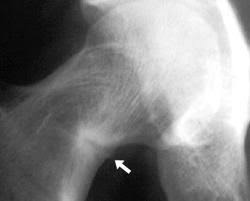

Medications for Stress Fractures You can take over-the-counter medications to manage pain. Initial treatment of a hip stress fracture may include X-rays a magnetic resonance imaging MRI scan or a bone scan to further evaluate your condition.

If an x-ray or MRI at the sports clinic confirms that youre experiencing a stress fracture in the hip the doctor will likely instruct you to rest. There are different operations which are. This depends on the fracture site and whether it is a simple crack or a displaced fracture.